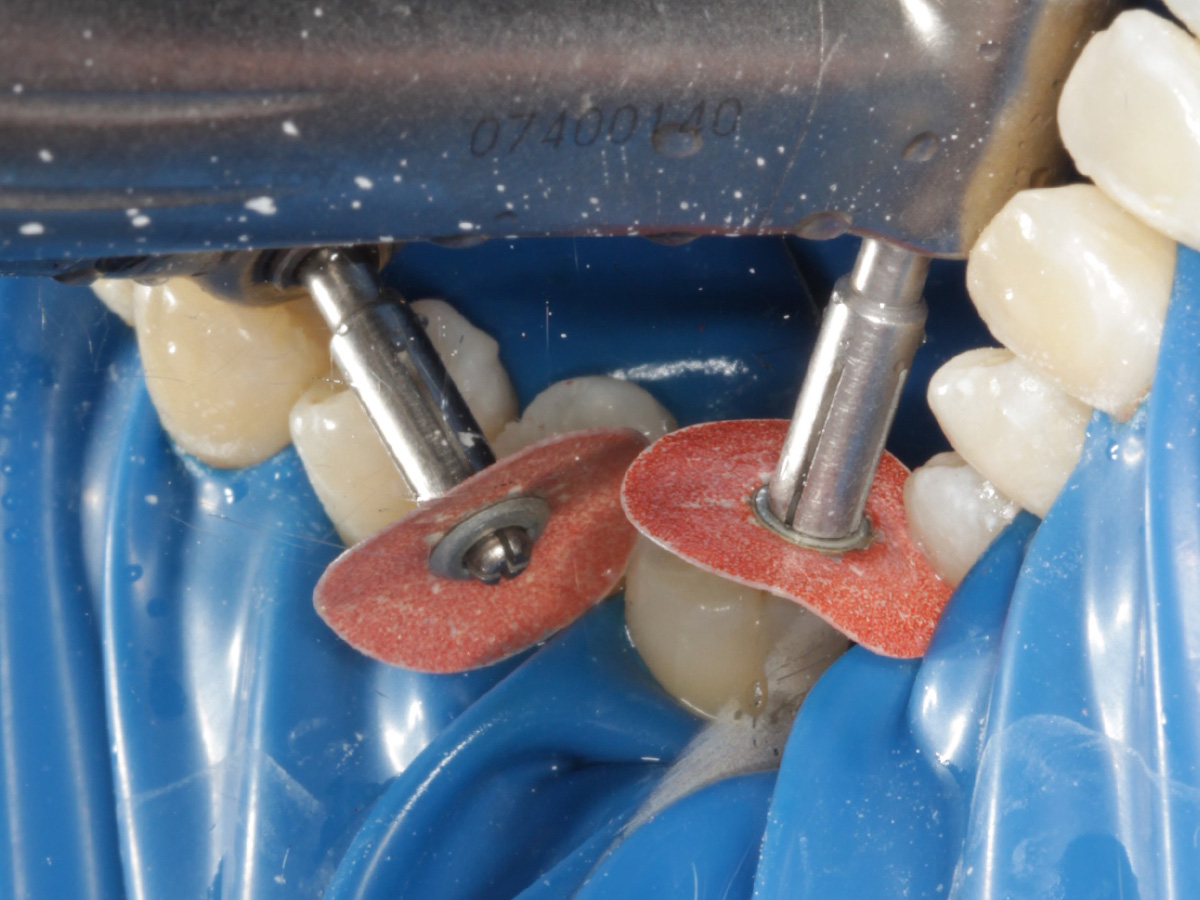

Abbildung 16

Überschussentfernung/ „Anpolieren“ u.a. trocken mit Sandpapierscheibe